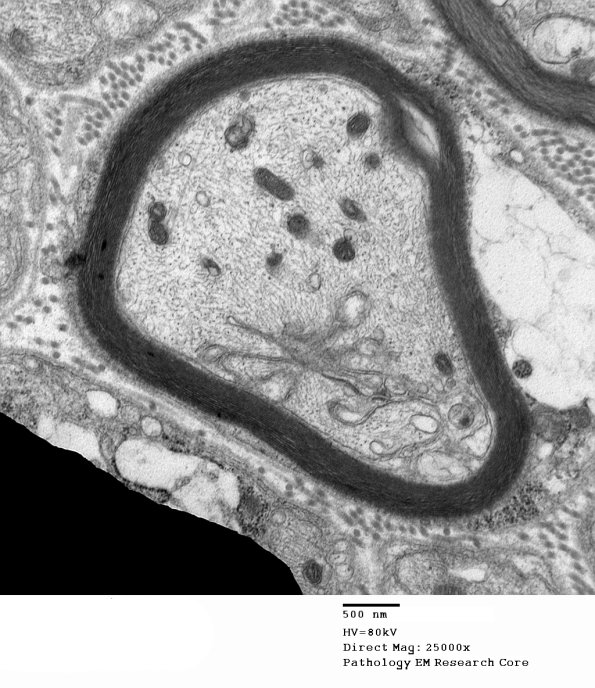

Invaginating processes are also present in some cases of actual axonal degeneration and demyelination. This represents another pathologic finding which is found in both artifact and genuine pathology. (electron micrographs)